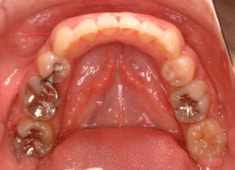

治療前